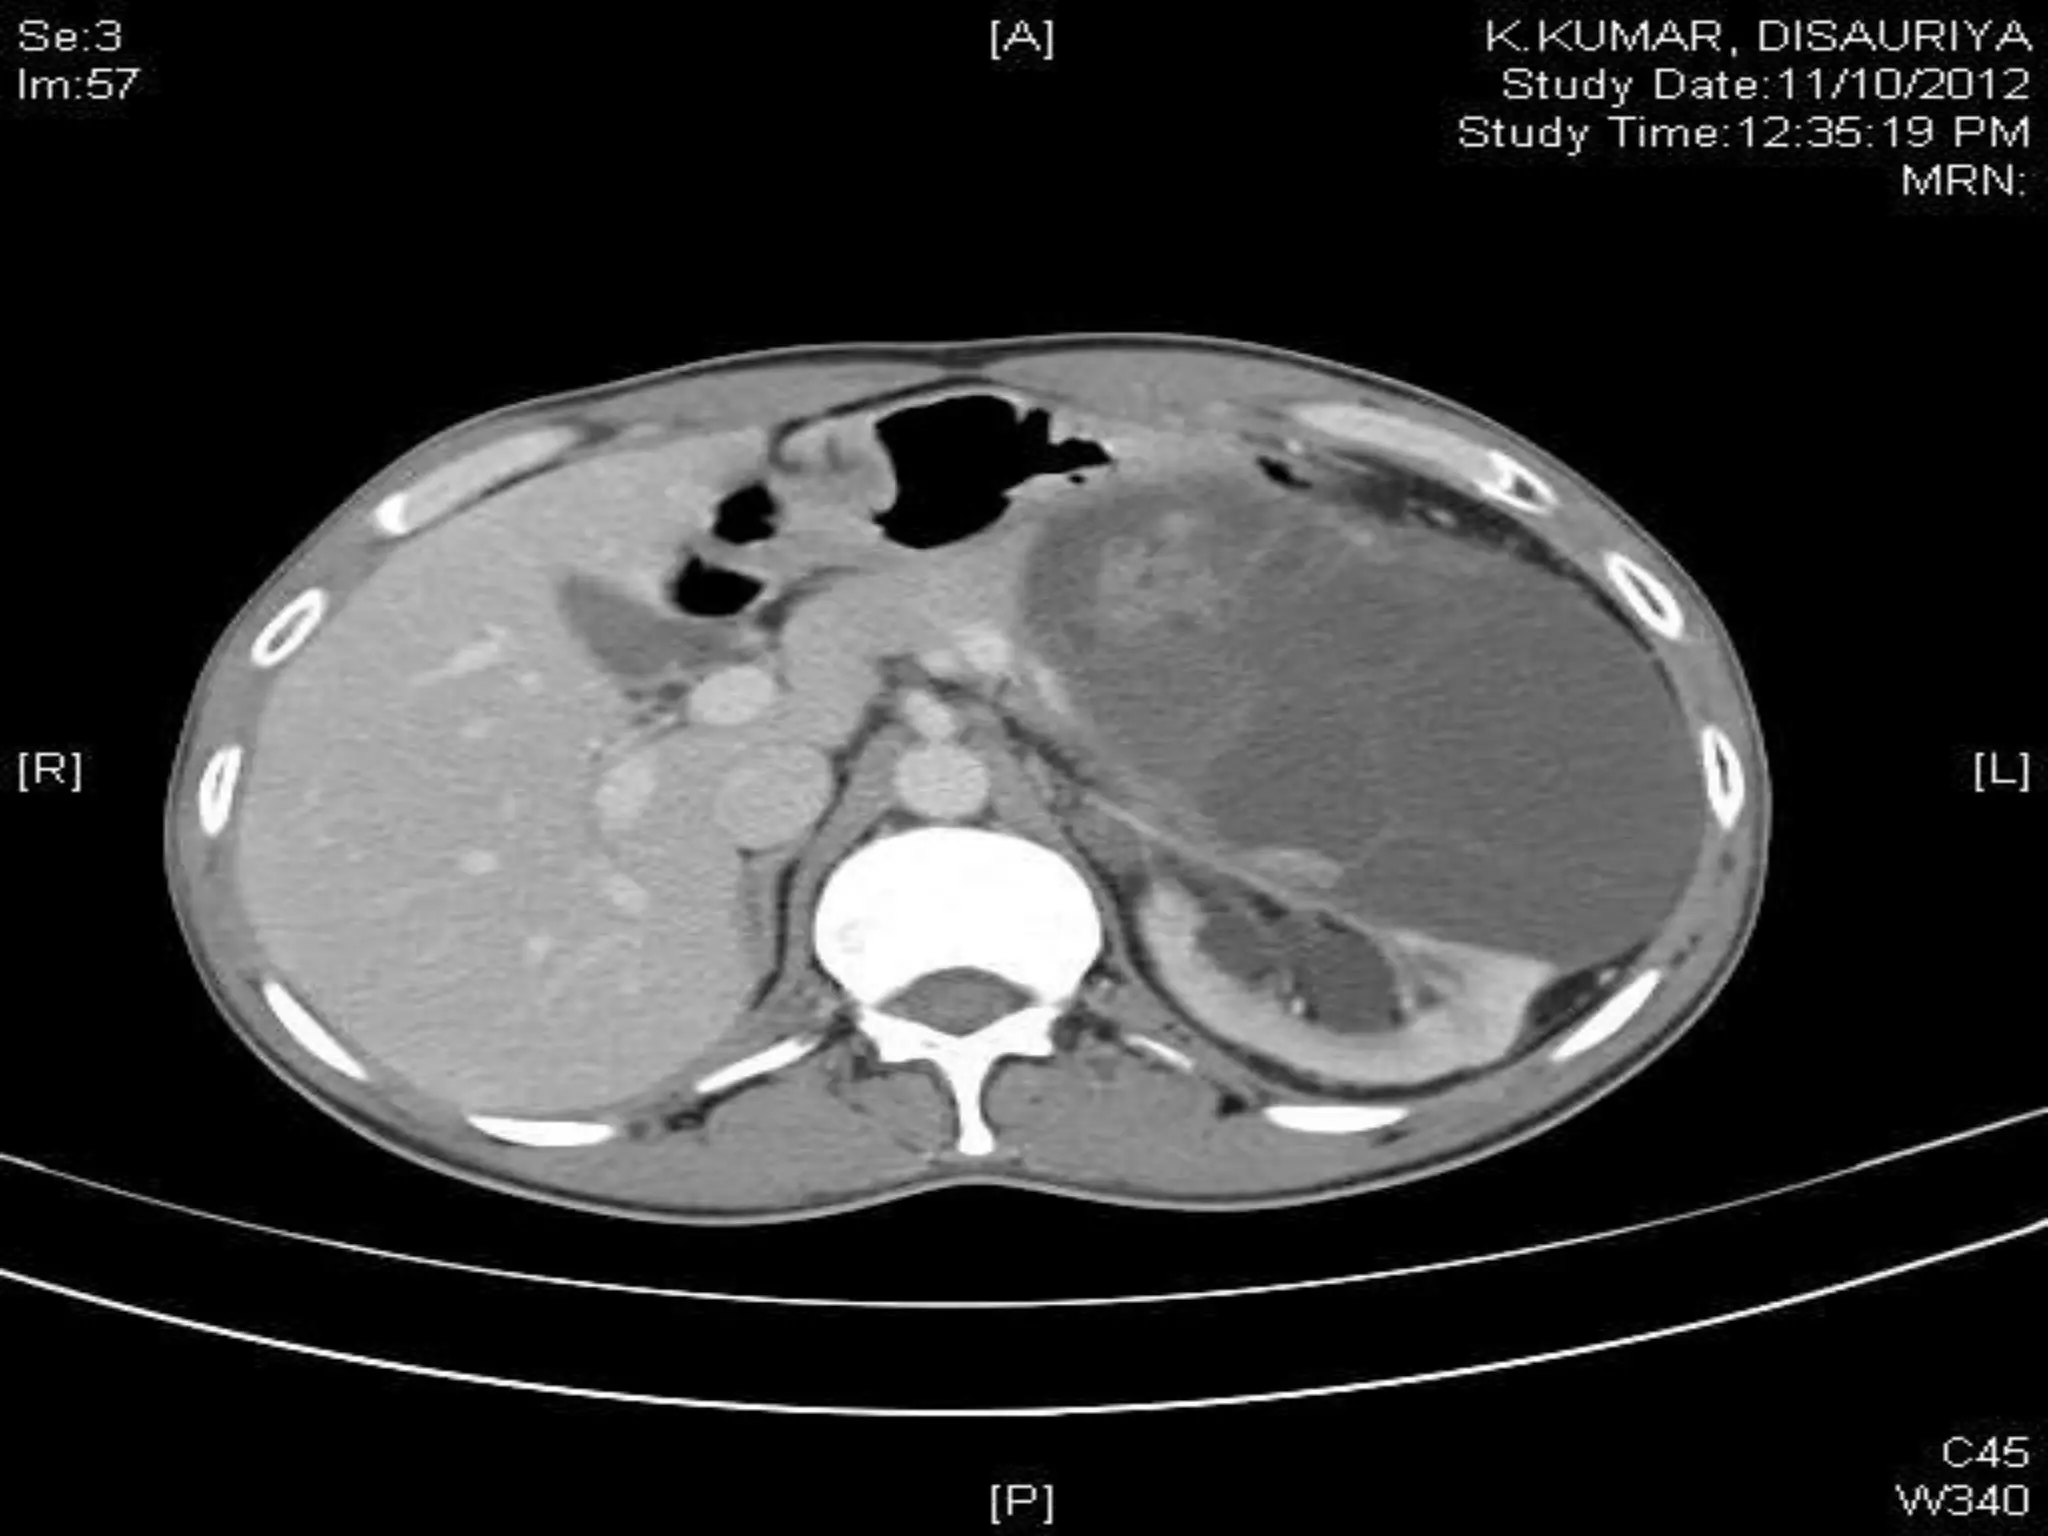

CHALLENGES IN RPLND

Retroperitoneal lymph node dissection kaushal